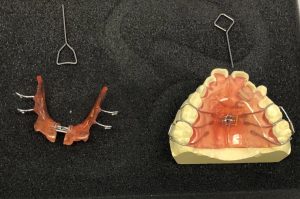

一般的によく行われている歯の矯正治療は、歯の表面や裏側にブラケットを固定し、ブラケットに通したワイヤーで力をかけながら歯を動かしていくという方法ですが、最近では透明のマウスピースを歯に装着するだけで、理想の歯並びに矯正できる方法が登場しています。

マウスピースシステムにはいくつかの種類がありますが、マウスピースは目立ちにくく、痛みも少なく、食事や歯磨きの際には、取り外しも自由という利便性もありますが、マウスピース矯正にはデメリットもあります。

小児期の予防的矯正(一次矯正)から

永久歯列期の矯正(二次矯正)

一次矯正は、3歳から6歳までの乳歯列期と6歳から12歳までの混合歯列期に行います。

顎の拡大床や各種トレーナーなどを使って予防的な矯正をします。

2次矯正は永久歯列期で、ブラケットワイヤーやマウスピースを使っての矯正になります。